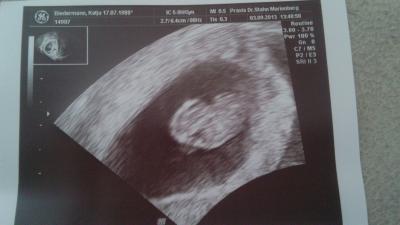

So bin wieder zurück. Krümel geht es gut. Herz hat schön geschlagen und unser krümel hat sogar geboxt. Das hämatom bereitet dem arzt noch große sorgen. Es ist genau so groß und so nah am baby wie letzte woche. Naja das es die nächsten 5 wochen abwarten und liegen, liegen, liegen

Bild zu Zurück vom FA! - Forum für April - Mamis